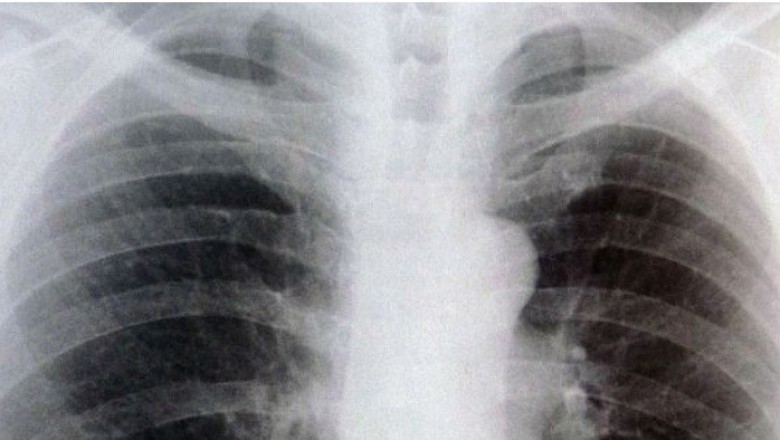

A lot of people possess a chest X-ray before they have surgery. This is known as a “pre-op” chest X-ray. “Pre-op” stands for preoperative, which implies that it truly is prior to an operation, or surgery. Get more information and facts about Radiografia de torax

When you have a heart or lung disease, you could choose to get a pre-op chest X-ray. It could show medical challenges, like an enlarged heart, congestive heart failure, or fluid about the lungs. These could imply that your surgery ought to be delayed or cancelled.